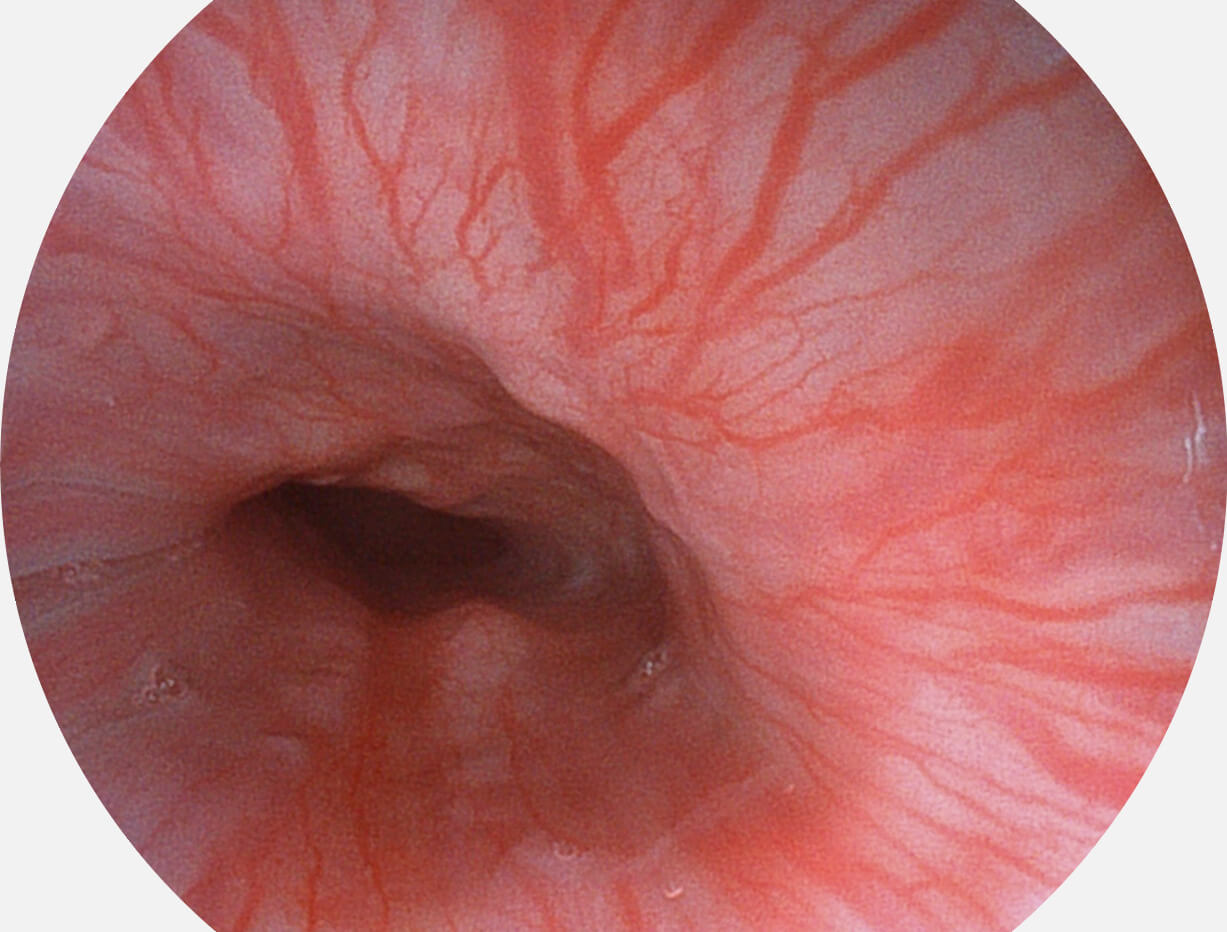

Spectral Focused lmaging, SFI

图像具有高亮度、高黏膜血管颜色对比度的特点,且不改变粘液、食物残渣、粪便的基本颜色,可在中远景下进行观察,助力消化道早期疾病的诊断。

白光图像